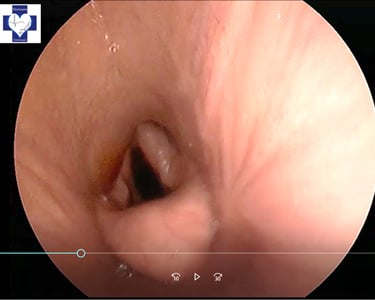

Longonderzoek (endoscopie, echografie, tracheal wash, radiografie)

Mobiele endoscopie/echografie - Consult aan huis

Heeft uw paard last van een aanhoudende of terugkerende hoest? Dan is het aangewezen om een endoscopie (cameraonderzoek) van de luchtwegen te laten uitvoeren. Hoesten wordt namelijk niet altijd veroorzaakt door astma. Tijdens het onderzoek kunnen we ook stalen nemen voor microscopisch en bacteriologisch onderzoek. Op basis van deze resultaten stellen we een behandelplan op maat van uw paard op.

In sommige gevallen is aanvullend een echografie van de longen aangewezen. Dit wordt steeds per situatie beoordeeld en met u besproken.

Longonderzoeken worden uitgevoerd op locatie in heel België, Nederland, Frankrijk, Duitsland en Luxemburg.